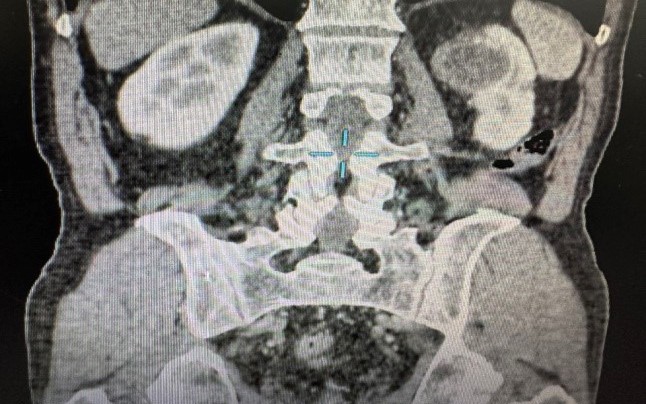

Theo bác sĩ Phong, đa phần nang thận đơn thuần lành tính, không cần điều trị, chỉ cần theo dõi định kỳ. Nhưng không phải bệnh nhân nào cũng hiểu sự khác biệt giữa nang lành và tổn thương dạng nang nghi ngờ ung thư. Ngay cả trên siêu âm, hình ảnh đôi khi không đủ rõ ràng để đưa ra kết luận chính xác. Nhiều trường hợp phải cần đến CT scan có tiêm thuốc cản quang hoặc MRI để phân biệt mức độ phức tạp của nang thận để đánh giá nguy cơ ung thư.

Bác sĩ Phong cho biết, từng tiếp nhận những bệnh nhân mang theo kết quả siêu âm của năm trước chỉ ghi nhận "nang thận". Tuy nhiên, khi tái khám tại Bệnh viện An Bình, tổn thương đó lại xuất hiện vách ngăn, dày bất thường và tăng sinh mạch máu - yếu tố nguy cơ cao của ung thư thận. Một số trường hợp, khối u đã phát triển đủ lớn khiến ê-kíp buộc phải thực hiện phẫu thuật cắt một phần thận để lấy trọn tổn thương nhưng vẫn bảo tồn tối đa chức năng nhu mô thận còn lại.